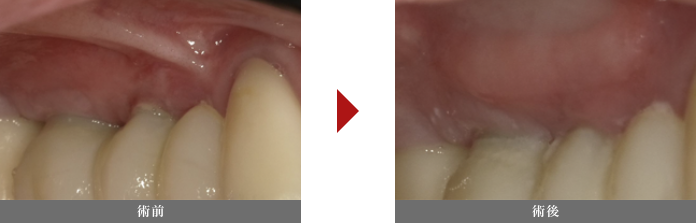

遊離歯肉移植術

遊離歯肉移植術とは

上皮付きの歯茎を歯茎がないところに移植する処置です。インプラントの周囲には歯茎が2mm程ないと歯ブラシがしにくかったり、炎症が進みやすいという論文があります。インプラント手術と同時にこの歯茎の量も考慮する必要があります。1mm~2mm程の厚みの歯茎を処理していくことになりますので非常に繊細です。

当院では通常の診療では約4倍のルーペを使用していますが、このような歯茎の繊細な処置の場合8倍以上拡大してみることができるマイクロスコープ(手術用顕微鏡)を用いて処置を行います。マイクロスコープを用いた治療と比べ、用いない治療の成功率は30%程下がると多くの論文や文献で示されていますが、このマイクロスコープを用いて手術をできる医院は道内でもごく僅かです。

当院では日常的にマイクロスコープを使った診療を行っているため、このよう難易度の高い治療にも対応することが可能です。

症例

50代女性 治療回数:1回 治療費:30,000円 リスク:歯肉壊死、出血